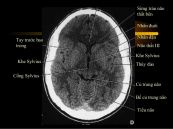

Nhũn não là hậu quả của tình trạng tắc mạch máu nuôi vùng não đó, gây nhồi máu não (cerebral infarct). Bài viết này sẽ nói rõ hơn về bệnh lý nhũn não động mạch não giữa, mời các bạn tham khảo!

Khi máu bị “ách tắc giao thông” hoàn toàn, không thể đem chất dinh dưỡng nuôi não thì tế bào não sẽ chết, xung quanh nhũn ra. Giới y học gọi hiện tượng này là chứng nhũn não. Bài viết này sẽ nói cụ thể về hội chứng Nhũn não động mạch não trước, mời các bạn tham khảo!